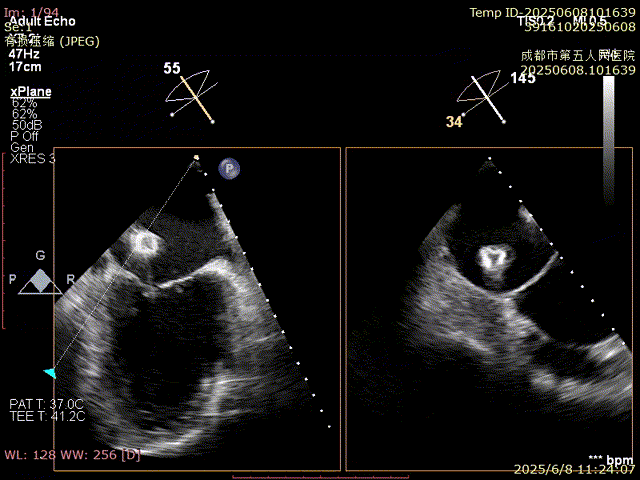

術(shù)前超聲

VFMR,反流2區(qū),新分型CCA型,MR重度(VC:3*14mm),A2:21mm,P2:10-11mm,AP:30mm,前后葉間3mm gap,MVA約5.1cm²